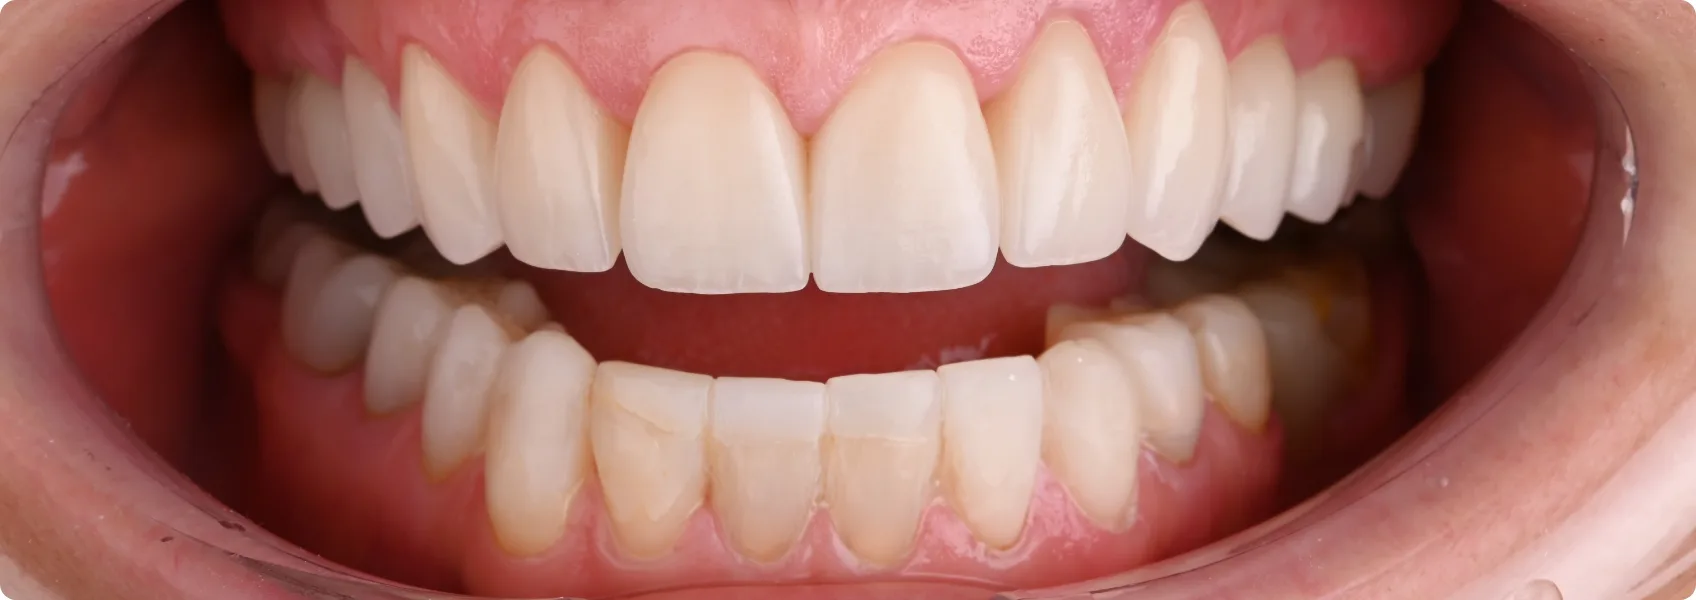

Finalnie doktor Ewa w łuku górnym założyła przygotowane korony pełnoceramiczne.

W łuku dolnym na zdjęciach widoczna jest jeszcze rekonstrukcja w formie tymczasowej – długoczasowej. Taka “tymczasówka” nie jest na stałe. Nie wygląda zbyt naturalnie, a po kilku miesiącach zaczyna przebarwiać się wskutek wnikania w materiał barwników z jedzenia. Można ją jednak nosić w oczekiwaniu na dalsze etapy leczenia.

Przywróciliśmy funkcję — prawidłowe kontakty pomiędzy zębami górnymi i dolnymi.

Genialnie wręcz odbudowane prowadzenia boczne i przednie sprawiły, że zęby przestały wreszcie nieprawidłowo trzeć o siebie. Doktor Ewa przywróciła nie tylko estetykę, ale przede wszystkim prawidłową funkcję zębów. Pacjentka przestała cierpieć na bolesną nadwrażliwość.

Korony pełnoceramiczne to estetyka z najwyższej półki. Dobrze zrobione — są nie do odróżnienia od naturalnych zębów.

Efekt leczenia? Uśmiech, który zachwyca naturalnością, subtelnym blaskiem i perfekcyjnym dopasowaniem. Pacjentka to wyjątkowo roześmiany, serdeczny człowiek. Dzięki nowym zębom zyskała więcej pewność siebie.